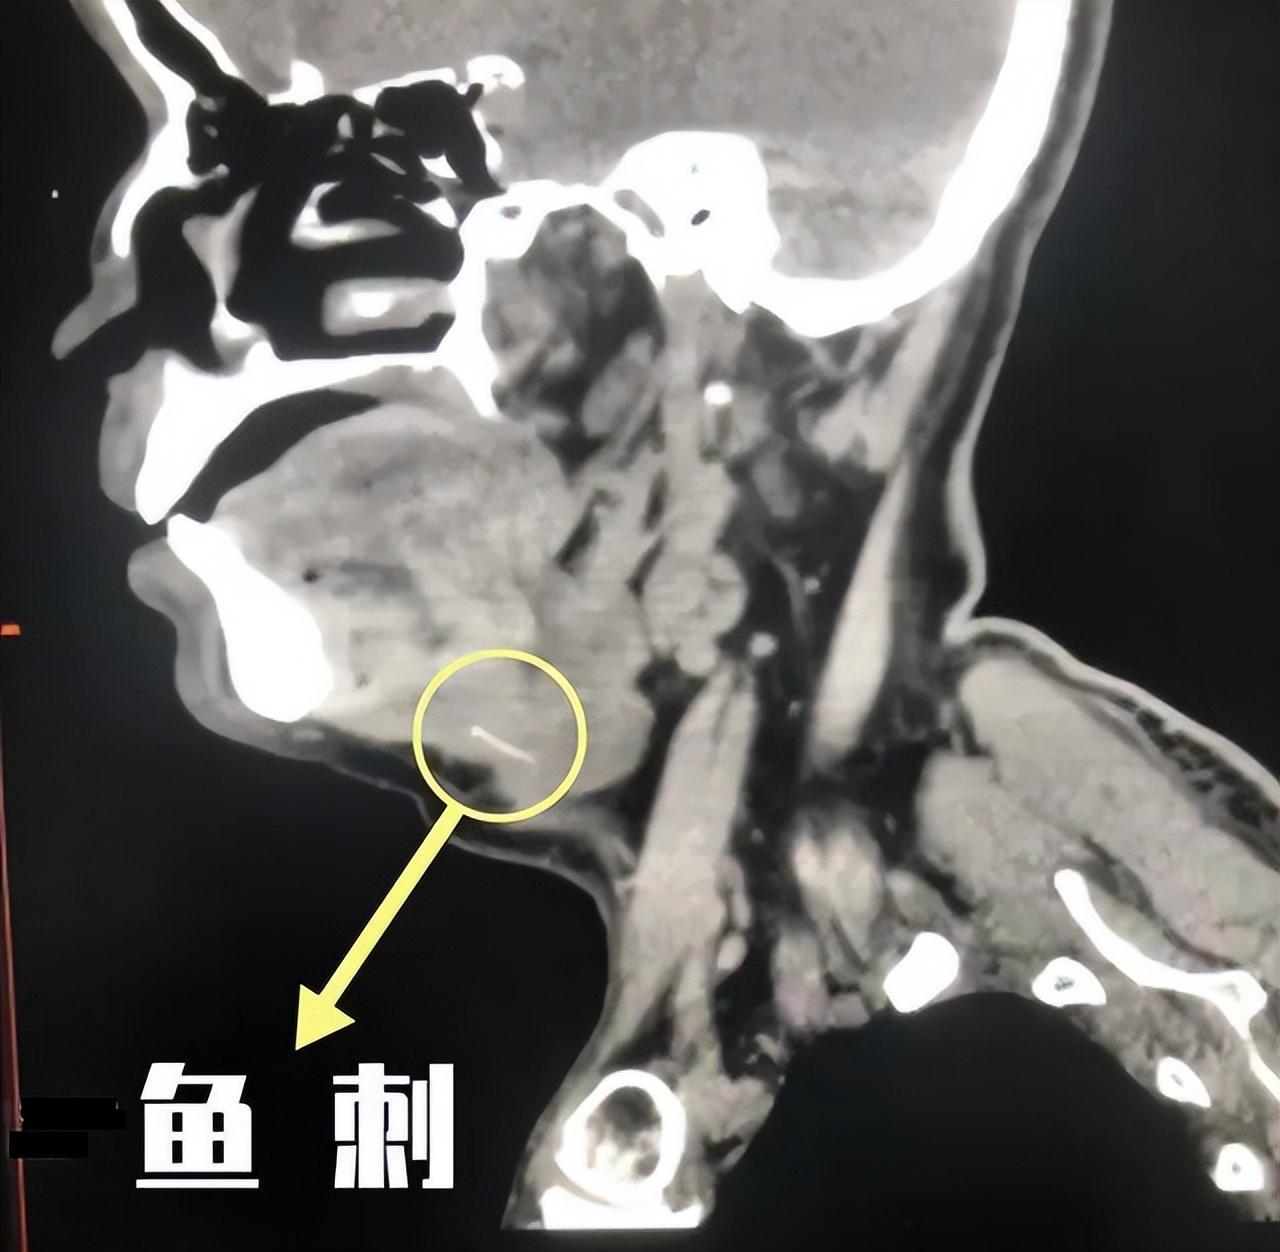

肉眼沒有找到魚刺,接下來就需要喉鏡來幫忙了,醫生打完麻藥後,就開始做喉鏡了。在喉鏡的輔助下,終於發現了魚刺,值得慶幸的是,魚刺並沒有卡在食道上,而是卡在了扁桃體旁邊的一個隱窩中。

發現魚刺位置後,醫生很快就幫忙把魚刺取出來了。看吧,就是這根魚刺,老婆取笑我:去用魚刺做根項鍊吧,掛脖子上,以後就能提醒你,喫魚要小心了。

大家可別小看魚刺卡喉哦,據醫生講,前陣子有個人魚刺卡喉,最終是開頸部才把魚刺取出來。